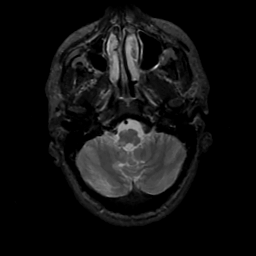

MR Study #3, February 24, 1991 -- Slice #8

[Home][Help][Clinical][Tour 1][Tour 2] Slice 8